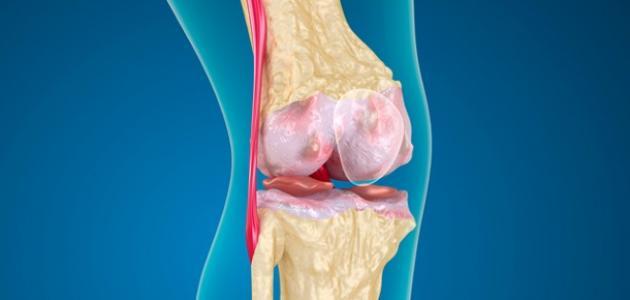

يكشف الدكتور محمد غانم، أخصائي جراحة العظام والمفاصل والكسور، عن أنواع وأعراض قطع الغضروف الهلالي للركبة، فضلا عن العلاج المناسب حسب نوع قطع الغضروف.

وعن أعراض قطع الغضروف الهلالي للركبة، يقول أخصائي العظام، أنه يتعرض الشخص لألم شديد في الركبة وخاصة عند قرار ثنيها وعند المشي، وهناك العديد من الأشخاص لا يتحركون بالشكل الجيد ويلاحظون المشكلة سريعا، ولابد من مراجعة الطبيب.

أنواع قطع الغضروف الهلالي للركبة

أما عن أنواع قطع الغضروف الهلالي للركبة، يشير طبيب العظام، إلى نوعان، الأول قطع إصابي، وهذا النوع يحدث نتيجة للحوادث أو التعرض للإصابات الرياضية، ويكون العلاج في اغلب الحالات هو التدخل الجراحي بالمنظار، إما استئصال الغضروف أو القيام بإصلاحه، وفي بعض الحالات من الممكن استخدام العلاج الطبيعي وتقوية عضلات الفخذ.

أما النوع الثاني الذي سلط الضوء عليه جراح العظام الدكتور محمد غانم، يطلق عليه «قطع تآكلي»، وهذا النوع يحدث نتيجة للتعرض للخشونة، مع تأكل مفصل الركبة، وخاصة عند كبار السن، وفي غالبية الأحيان لا يستدعي الامر تدخل جراحي، والعلاج يتم عن طريق جلسات للعلاج الطبيعي لتقوية الأربطة والعضلات حول الركبة.

ويضيف أخصائي العظام أنه عند تشخيص قطع الغضروف ومعرفة أفضل طريقة علاج، حيث ان المريض لابد من إجراء فحوصات وأشعة عادية ورنين مغناطيسي، شارحا أنه في حالة الاحساس بألم في الركبةأو في حالة شك المريض في نوع الإصابة لابد من زيارة الطبيب لمعرفة الحالة والتشخيص المناسب.